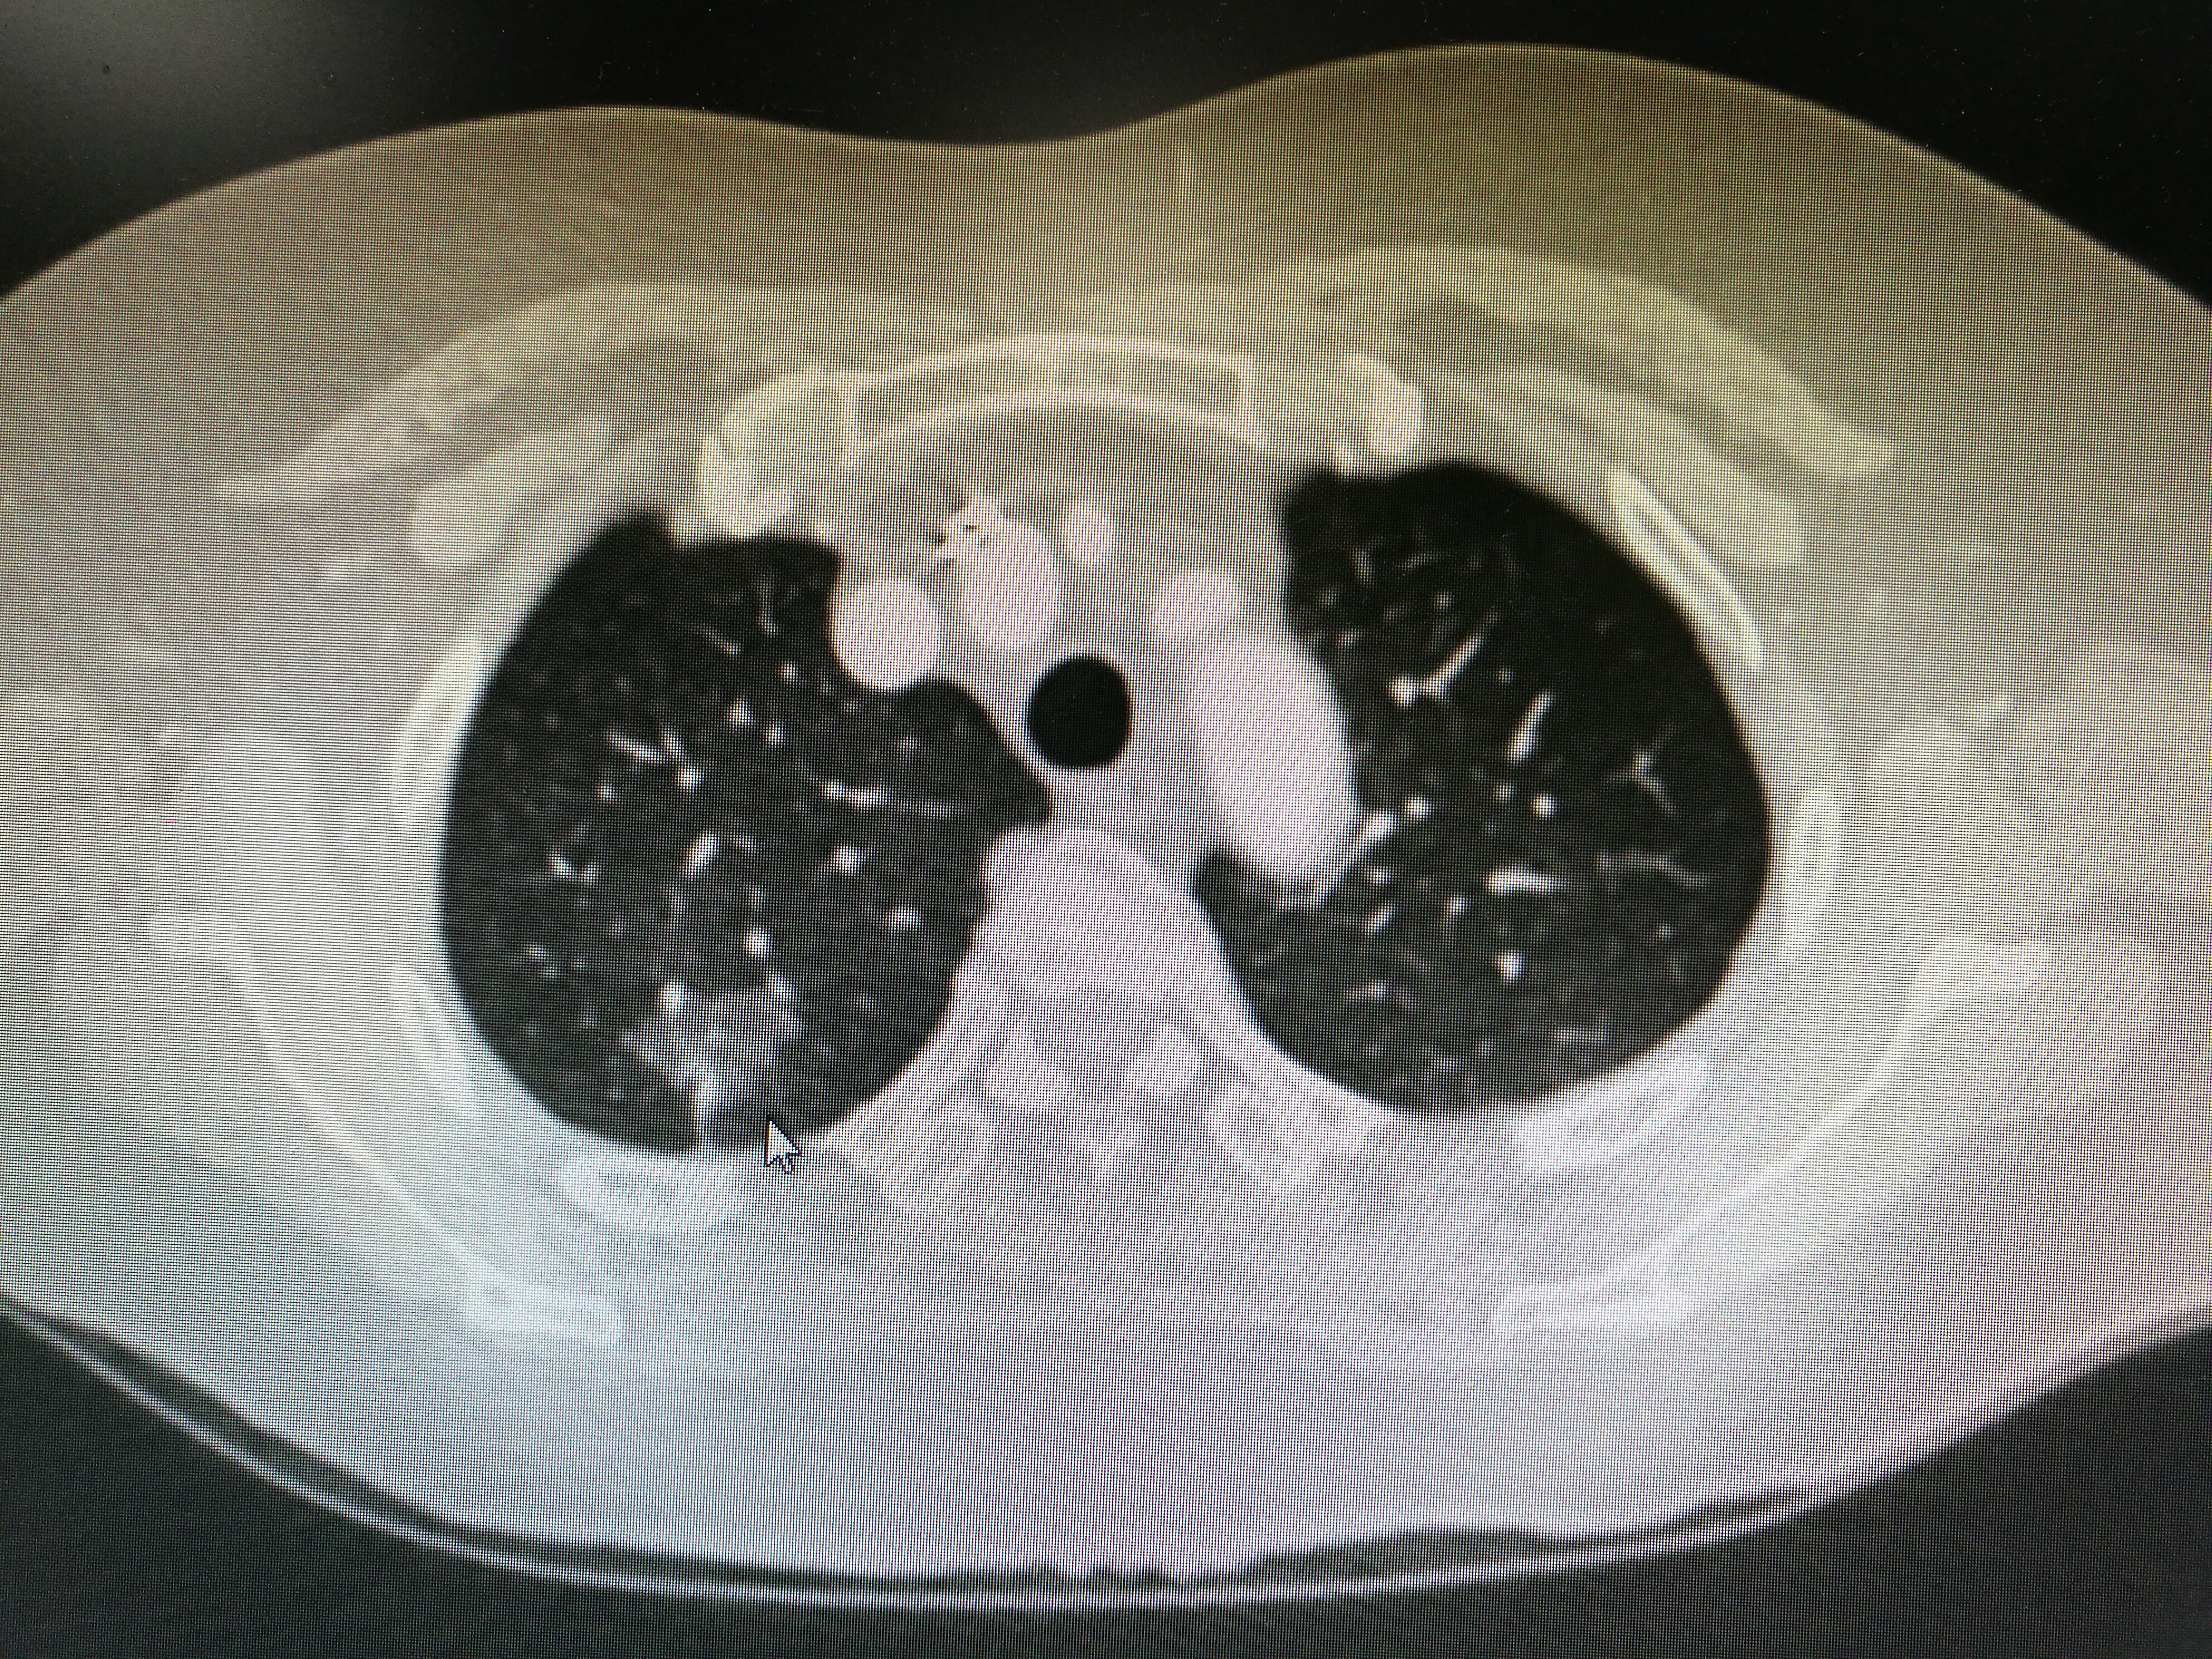

关注:肺部结节会自己消失吗?

对于肺部结节,如果没有予以相关治疗,一般来说是不会自己消失的。在体检的时候发现有肺部小结节的存在,其形成小结节的原因有可能是由于结核感染后遗留的结节,也有可能是由于肺部肿瘤性的结节。当然也不排除是炎症性的结节,如果是炎症性的结节,经过抗炎治疗后,是会消失的。

很多人不明白,按照医师的话,肺部结节是不会自己消失的,但复查的CT上却明明显示已经消失了,那这又是怎么回事呢?根据临床经验,肺部结节之所以会“消失”,可能有以下几种情况:

2、未被扫描到:如果是只有几毫米的肺部结节,还有一种可能的情况是,CT的每一层厚度都超过它,没有扫描到,而被误认为是“消失”了。

很多人查出肺部结节,以为只是小事,总会置之不理。特别是在肺部结节“消失”的时候,便感觉已经摆脱了疾病困扰,无需过分担心。在未予治疗的情况下,对于“消失”的肺部结节不能太大意。因为“消失”并不代表没问题,只是肉眼无法看见,影像学检查也有一定的漏诊率。此时,一定要注意,及时去医院进行全面的防癌筛查。